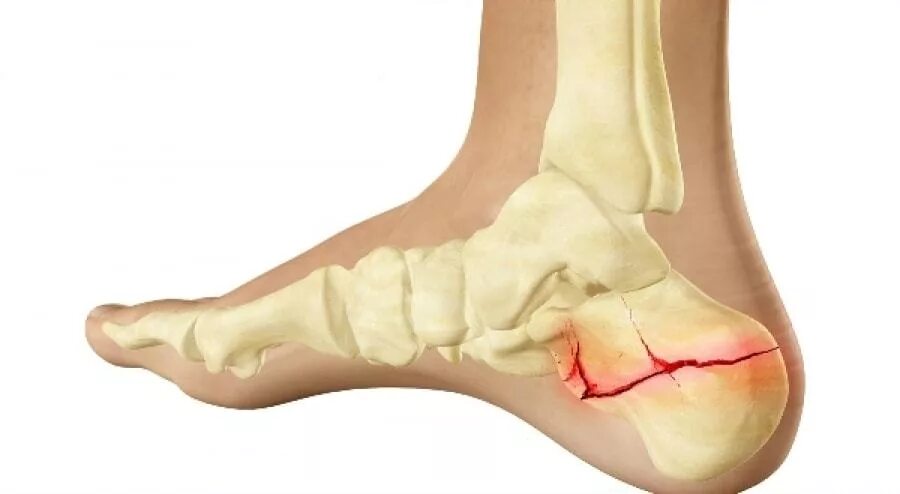

Трещина в кости ноги сколько